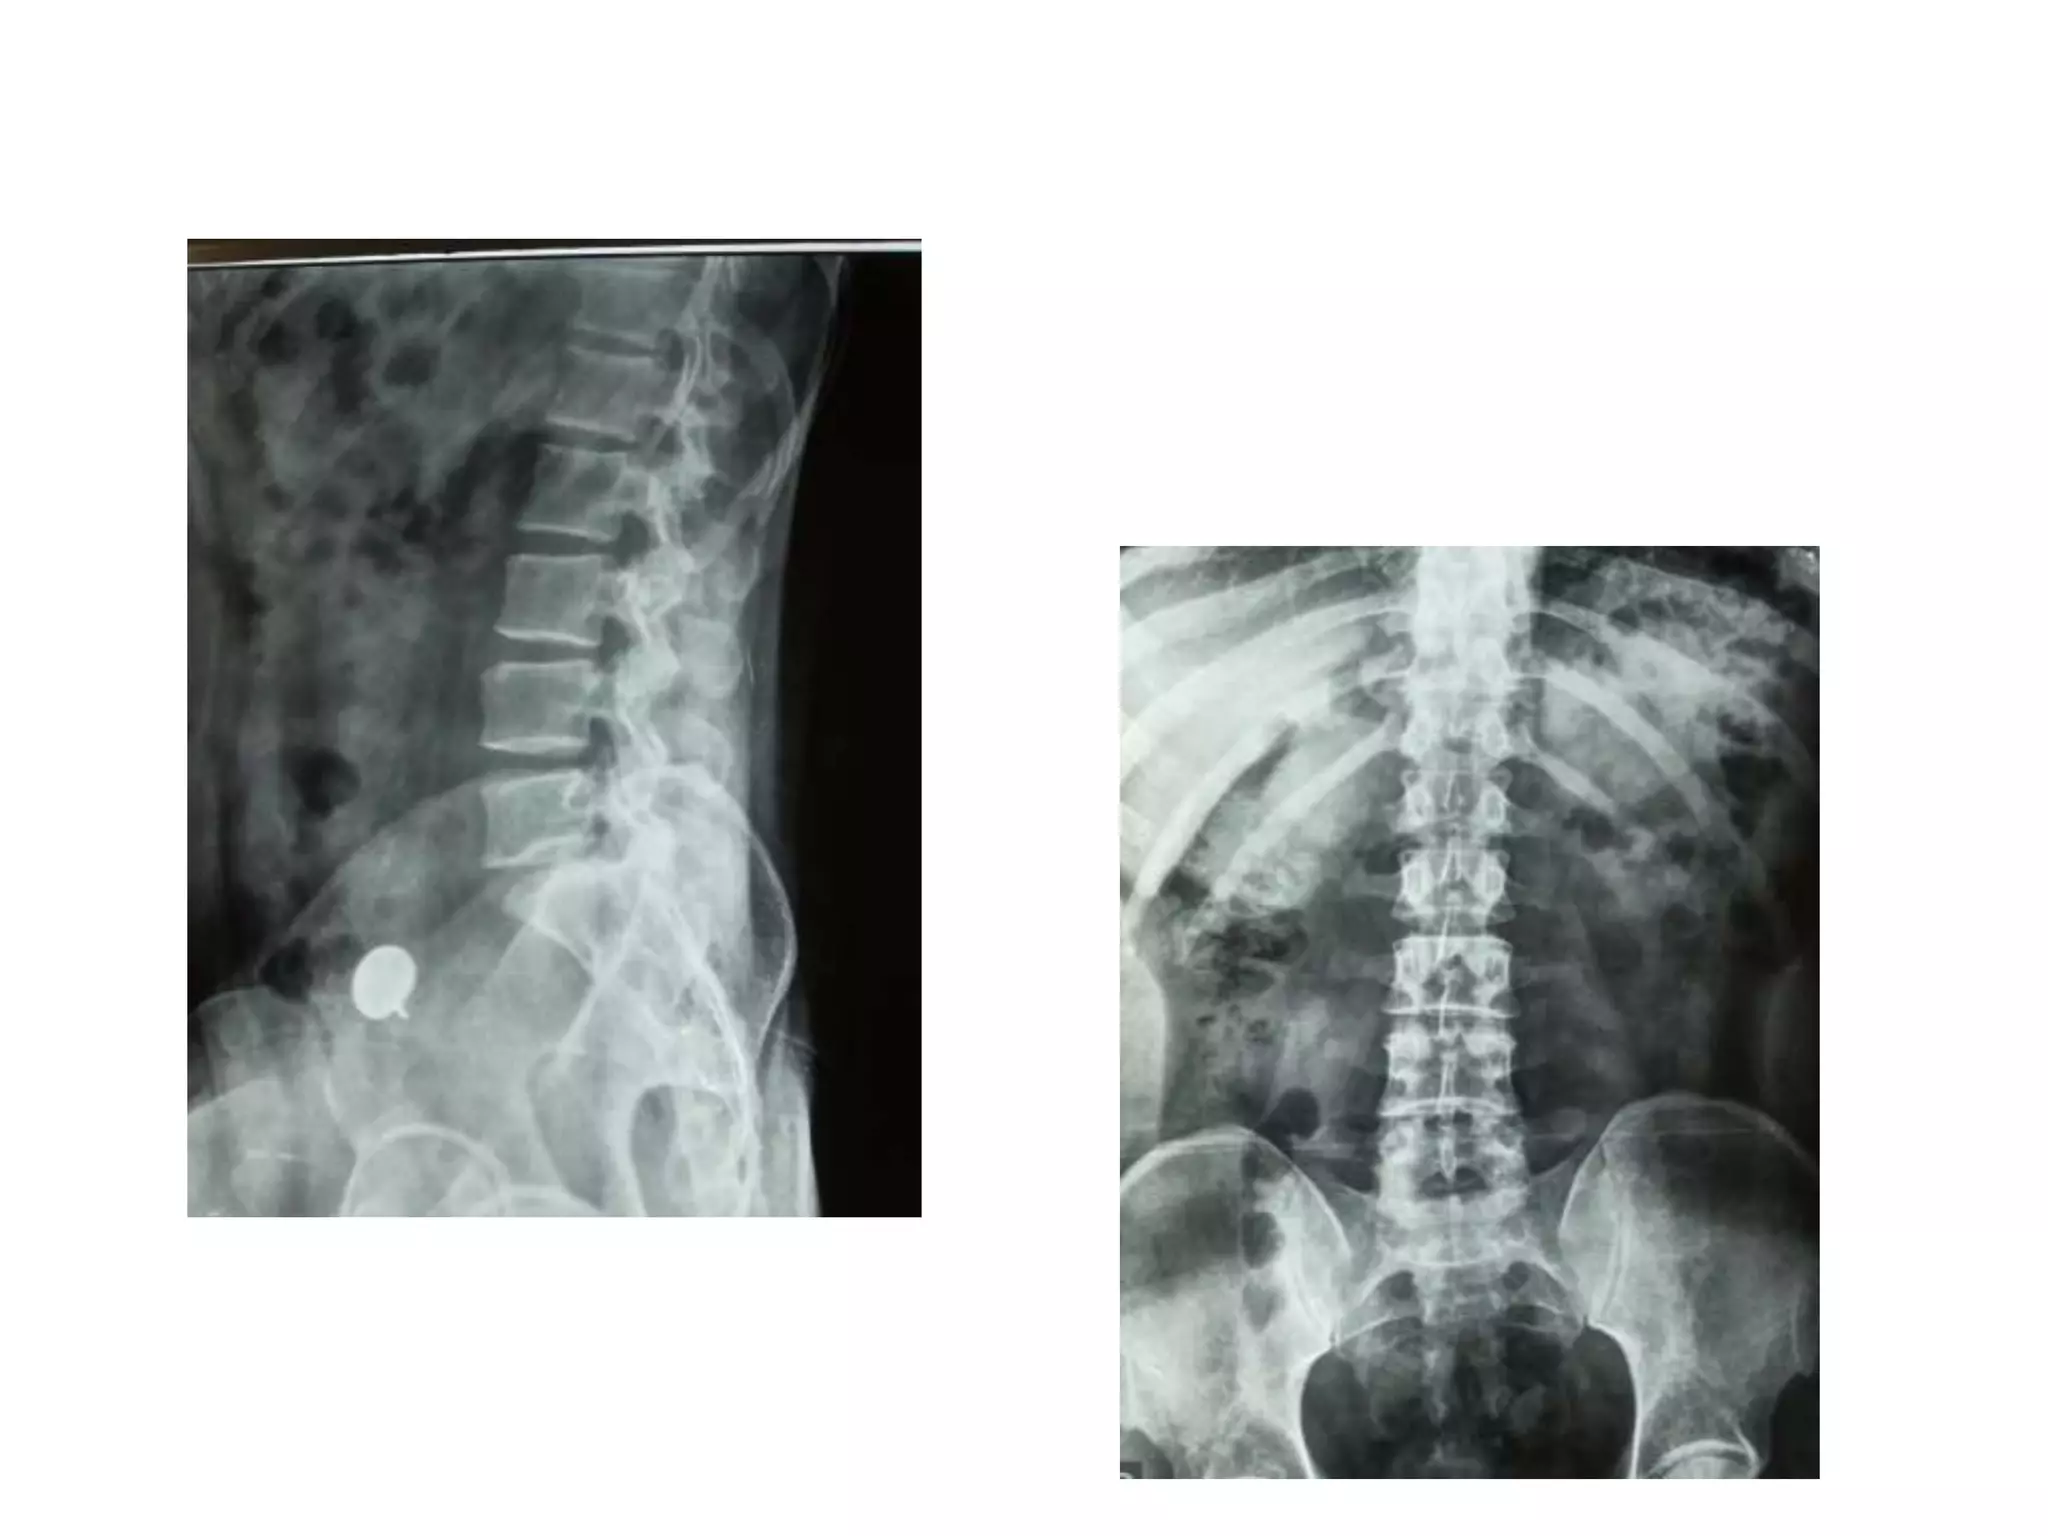

X ray

Post operative x ray